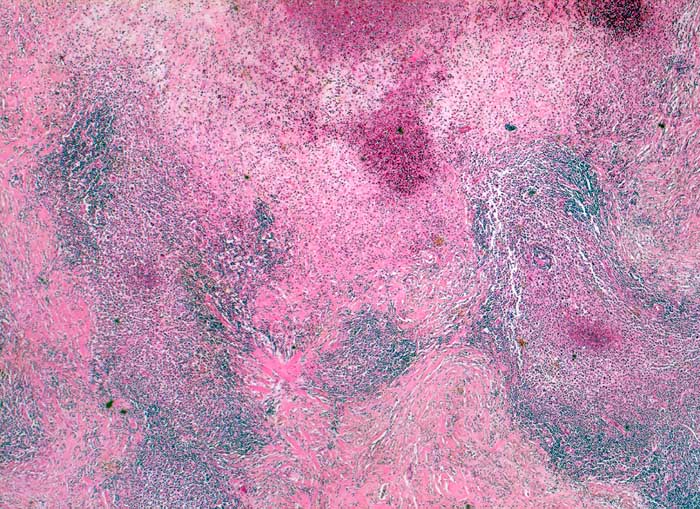

PathoPic – image database / PathoPic ID 5576 - Hodgkin Lymphom noduläre Sklerose

Hodgkin Lymphom noduläre Sklerose

maligner Tumor

Lymphknoten, supraklavikulär

Lymphatische Gewebe, KM, Milz

Von breiten Bindegewebszügen durchsetzter Lymphknoten

Zervikale Lymphadenopathie.

Histologie

25